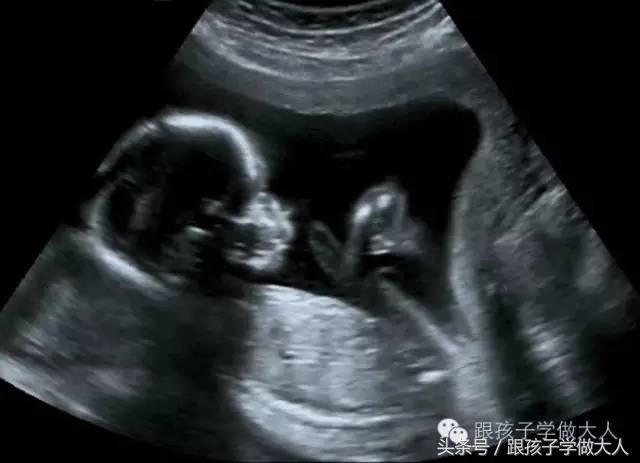

①孕20-24周左右,观察胎头,脊柱、心脏、肺、胃肠、双肾、膀胱、外生殖器、四肢,此时是四肢等大的畸形检查的最佳时期;

②孕24一32周,重点观察胎宝宝鼻唇部,心脏,可发现鼻唇部、心脏的畸形。